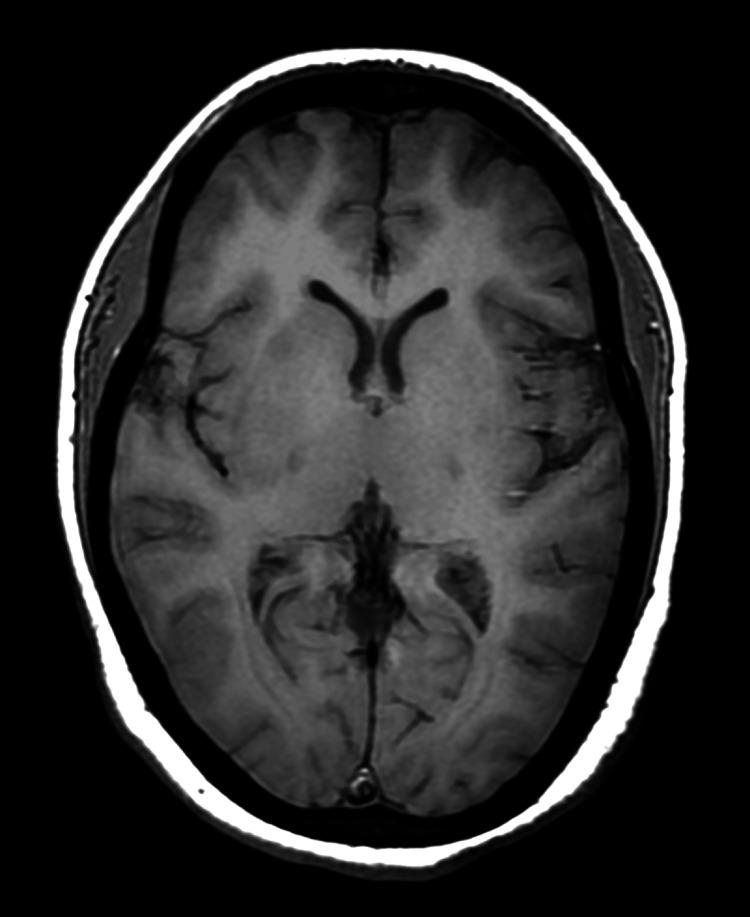

后部可逆性脑病综合征(PRES)的非典型表现:一例病例报告及文献复习

Atypical Presentation of Posterior Reversible Encephalopathy Syndrome (PRES): A Case Report and Review of the Literature.

Posterior reversible encephalopathy syndrome (PRES) is a reversible clinico-radiological entity characterized by acute neurological symptoms and white matter vasogenic edema that commonly affects the posterior occipital and parietal lobes of the brain. Patients with this condition usually present with complaints of headache, encephalopathy, seizures, or visual disturbances. Nystagmus and periodic alternating gaze are rarely reported presentations of PRES patients. Similarly, involvement of the brainstem, cerebellum, basal ganglia, and other cerebral areas are atypical findings on brain imaging. Early diagnosis and immediate treatment can reverse both the clinical and radiological features of PRES.

摘要

后部可逆性脑病综合征(PRES)是一种可逆的临床放射学实体,其特征为急性神经症状和白质血管源性水肿,通常影响大脑的枕叶后部和顶叶。患有这种疾病的患者通常会出现头痛、脑病、癫痫发作或视觉障碍等症状。眼球震颤和周期性交替凝视是PRES患者很少见的表现。同样,脑干、小脑、基底神经节和其他脑区受累在脑部影像学检查中属于非典型表现。早期诊断和及时治疗可使PRES的临床和放射学特征得到逆转。